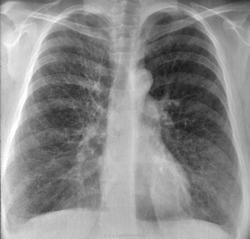

При поступлении одышка, кашель, Т до 37. "Рентгенкартина пневмонии справа, пневмосклероз, эмфизема. Киста, булла слева?" Прошу прощение за качество, снимки"с рук".

По "просьбам трудящихся" не выкладываю все сразу. Но уж ОЧЕНЬ эмфизема, режимы выдал - экспонометр("на среднего"), проявка - автомат. Снимки в реале - темнее ночи. Что тут больше всего смущает справа?

Ссылки на КТ еще не смотрел, но давайте разберемся по классике (хотя из-за качества не хочется :(

На фоне эмфиземы и булл имеется размытая интенсивная инфильтрация в S8 справа и гидроторакс в наддиафрагмальной зоне. НО... Уровень-то горионтальный, значит есть сообщение с воздухом. Пути два: снаружи (пункция) и изнутри (прорыв буллы, абсцесса, кисты). На реформатах жидкости нет.

Добавила аксиалы с видео в начале темы. По КТ: ну, буллы, ну, компрессия нижней доли и неполная - средней. Гидропневмоторакс справа. Эмфизема. Рака не увидела.

Ну, рака бы я конечно не поставил. КТ-признаки эмфиземы легких, буллезной эмфиземы, пневмогидроторакса в переднем отделе справа; сзади справа, считаю большая киста/кисты с уровнем жидкости.